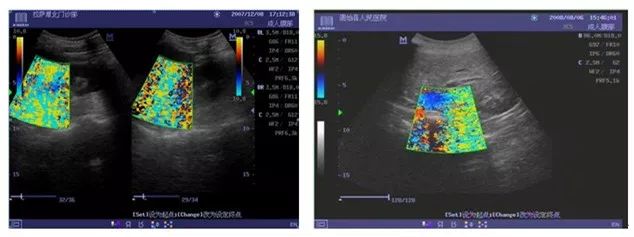

原因一:探头线缆屏蔽层断裂,致使干扰电磁场被引入出现图像干扰问题。

改进措施:2010.2月改用耐拉拽、弯曲强度更高的探头线缆。

原因二:探头屏蔽线与信号地方式不合理。

改进措施:改善探头蔽屏线的连接方式。